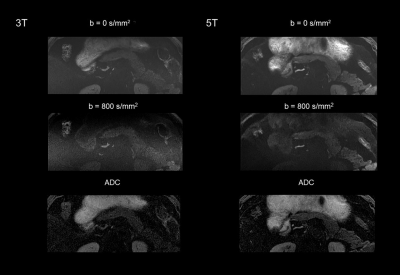

Figure 1-3 shows an example of 5T MRI and 3T MRI for each sequence. Interobserver agreement in image quality and artifacts was substantial to excellent for all sequences (κ > 0.7). Compared to the 3T examination, T1-weighted and DWI sequence at 5T showed significantly better image quality and comparable artifacts. For T2-weighted images, there was no significant difference in image quality ratings and the presence of artifacts between 3T and 5T. The mean ratios of SNR at 5 T to 3T of the T1-weighted images for the pancreatic head, body, and tail were 1.45, 1.35, and 1.48, respectively. For T2-weighted images, the corresponding ratios were 1.16, 1.33, and 1.39, respectively. For the DWI images (b = 800 s/mm2), the corresponding ratios were 1.29, 1.40, and 1.24, respectively. The SNRs of all the sequences were significantly higher at 5T than at 3T (P < 0.05 for all comparisons). For both 3T and 5T, mean ADC values on the pancreatic head were significantly higher than those of the tail (P = 0.016 for 3T, and P = 0.018 for 5T), while no significant difference was observed between the pancreatic head and body (P = 0.679 for 3T, and P = 0.445 for 5T). There was no significant difference in mean ADC values and CV of ADC between 3T and 5T (P > 0.05 for all comparisons).

Figure 3. Diffusion-weighted imaging with reduced field-of-view at 3T and 5T from the same participant.